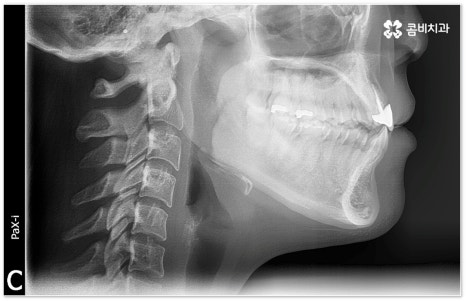

희고 가지런한 치아를 드러내며 환하게 웃는 사람을 보면 자기도 모르게 호감이 가곤하죠, 이처럼 대인 관계에서 치아는 좋은 인상을 만드는 데 심미적으로 큰 역할을 할 뿐 아니라 식사시 음식물을 저작하고 발음을 제대로 하는 데도 많은 도움을 주기 때문에 만약 타고난 치아가 삐뚤어졌거나 위아래 교합이 제대로 맞지 않는다면 이를 기능적 심미적으로 바로잡아 주기 위해서 치아 교정 치료를 고려해 볼 수 있습니다.

이때 성장기 청소년이 아니면 교정 치료를 받을 수 없는지, 교정 치료에 적기가 따로 정해져 있는지 궁금해 하시는 분들이 있는데 관련 기술의 발달로 나이에 크게 구애받지 않고 각자의 상황에 맞게 치료를 진행할 수 있으니 먼저 꼼꼼한 진단 및 상담을 받아보시길 바라고 있어요.

특히 업무적으로나 생활적으로 대인 관계가 활발하신 중장년 성인분들의 경우 치료 기간이 너무 오래 걸리지 않는지, 치아교정장치 가 너무 눈에 띄지는 않는지 궁금해 하시는 경우가 많이 있는데요. 말씀드렸던 것처럼 기술이 발달하면서 다양한 치아교정장치 가 나와있고 치아교정장치 자체는 결과에 크게 영향을 주지 않으므로 몇몇 케이스를 제외하면 환자분들께서 중요하게 생각하는 바 (심미성, 합리성 등) 를 반영할 수 있는 여지가 많이 있기 때문에 숙련된 의료진과 충분히 상담하셔서 각각의 장단점을 잘 살펴보시고 자신에게 꼭 맞는 장치를 고르시면 되니 크게 걱정하실 필요는 없을 거예요.

적지 않은 치아교정 비용 역시 치료 시작을 망설이시는 이유가 될 수 있는데요. 그렇다고 해서 치과를 선택할 때 가격적인 메리트만 생각하시기 보다는 교정 치료의 목적이 앞으로 남은 평생 동안 건강하게 사용해야 할 치아의 기능적 심미적인 개선에 있는 만큼 해당 임상 분야의 경험이 풍부하고 뛰어난 노하우를 가지고 있는 의료진과 함께 하는데 초점을 맞추시길 당부드리고 있어요. 또한 처음부터 끝까지 책임 진료하고 사후 관리 역시 철저하게 케어되는 곳인지, 3D CT와 같은 정밀 검진 장비를 갖추고 있는 곳인지 여부도 중요하기 때문에 이런 부분도 함께 살펴보시면 좋을 거예요. 환자 개개인에 맞춤 치료 계획을 세워 무리하지 않은 치아 이동을 통해 전체 구강 건강을 증진시키는 방향으로 교정 치료를 하기 위해서는 이와 같이 의료진의 숙련도 외에도 케어 시스템이나 장비 같은 부분을 꼼꼼하게 체크해 보시는 것이 치과를 선택하는 데 도움이 될 수 있습니다.

치아 교정 치료에 적기가 정해져 있는 것은 아니지만 아래 앞니가 윗 앞니보다 앞으로 물리는 반대교합이나 심각한 주걱턱과 같은 부정교합 등 몇몇 케이스에 있어서는 잇몸뼈가 아직 다 굳어지지 않은 성장기에 치료를 시작하는 것이 상하악의 균형을 잡아주고 교합을 맞추는데 좀 더 효율적일 수 있기 때문에 아이의 치열이 삐뚤어진다면 영구치가 나오기 시작할 때부터 치과에 내원하셔서 검진과 상담을 받아보실 필요가 있어요. 치과에 주기적으로 방문하여 검진 및 스케일링 등을 받으면서 혹시 교정 치료가 필요하지 않은지 여부를 확인하고 언제 시작하는 것이 좋을지 지속적인 관찰을 통해 맞는 시기를 조율해 봐도 좋을 거예요.